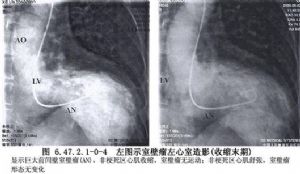

关于室壁瘤的外科治疗早在1944年就已开始,直到1958年Cooley方在体循环下进行直视切除手术,包括最大限度切除纤维瘢痕组织和对左室切口做线形缝合,这一手术方法一直沿用了一个相当长时间,到20世纪80年代后期Dor和Jatene方开始提出了更符合左室形态和保存左室功能的手术方法(表6.47.2-1),影像学表现见下图(图6.47.2.1-0-3~6.47.2.1-0-5)。